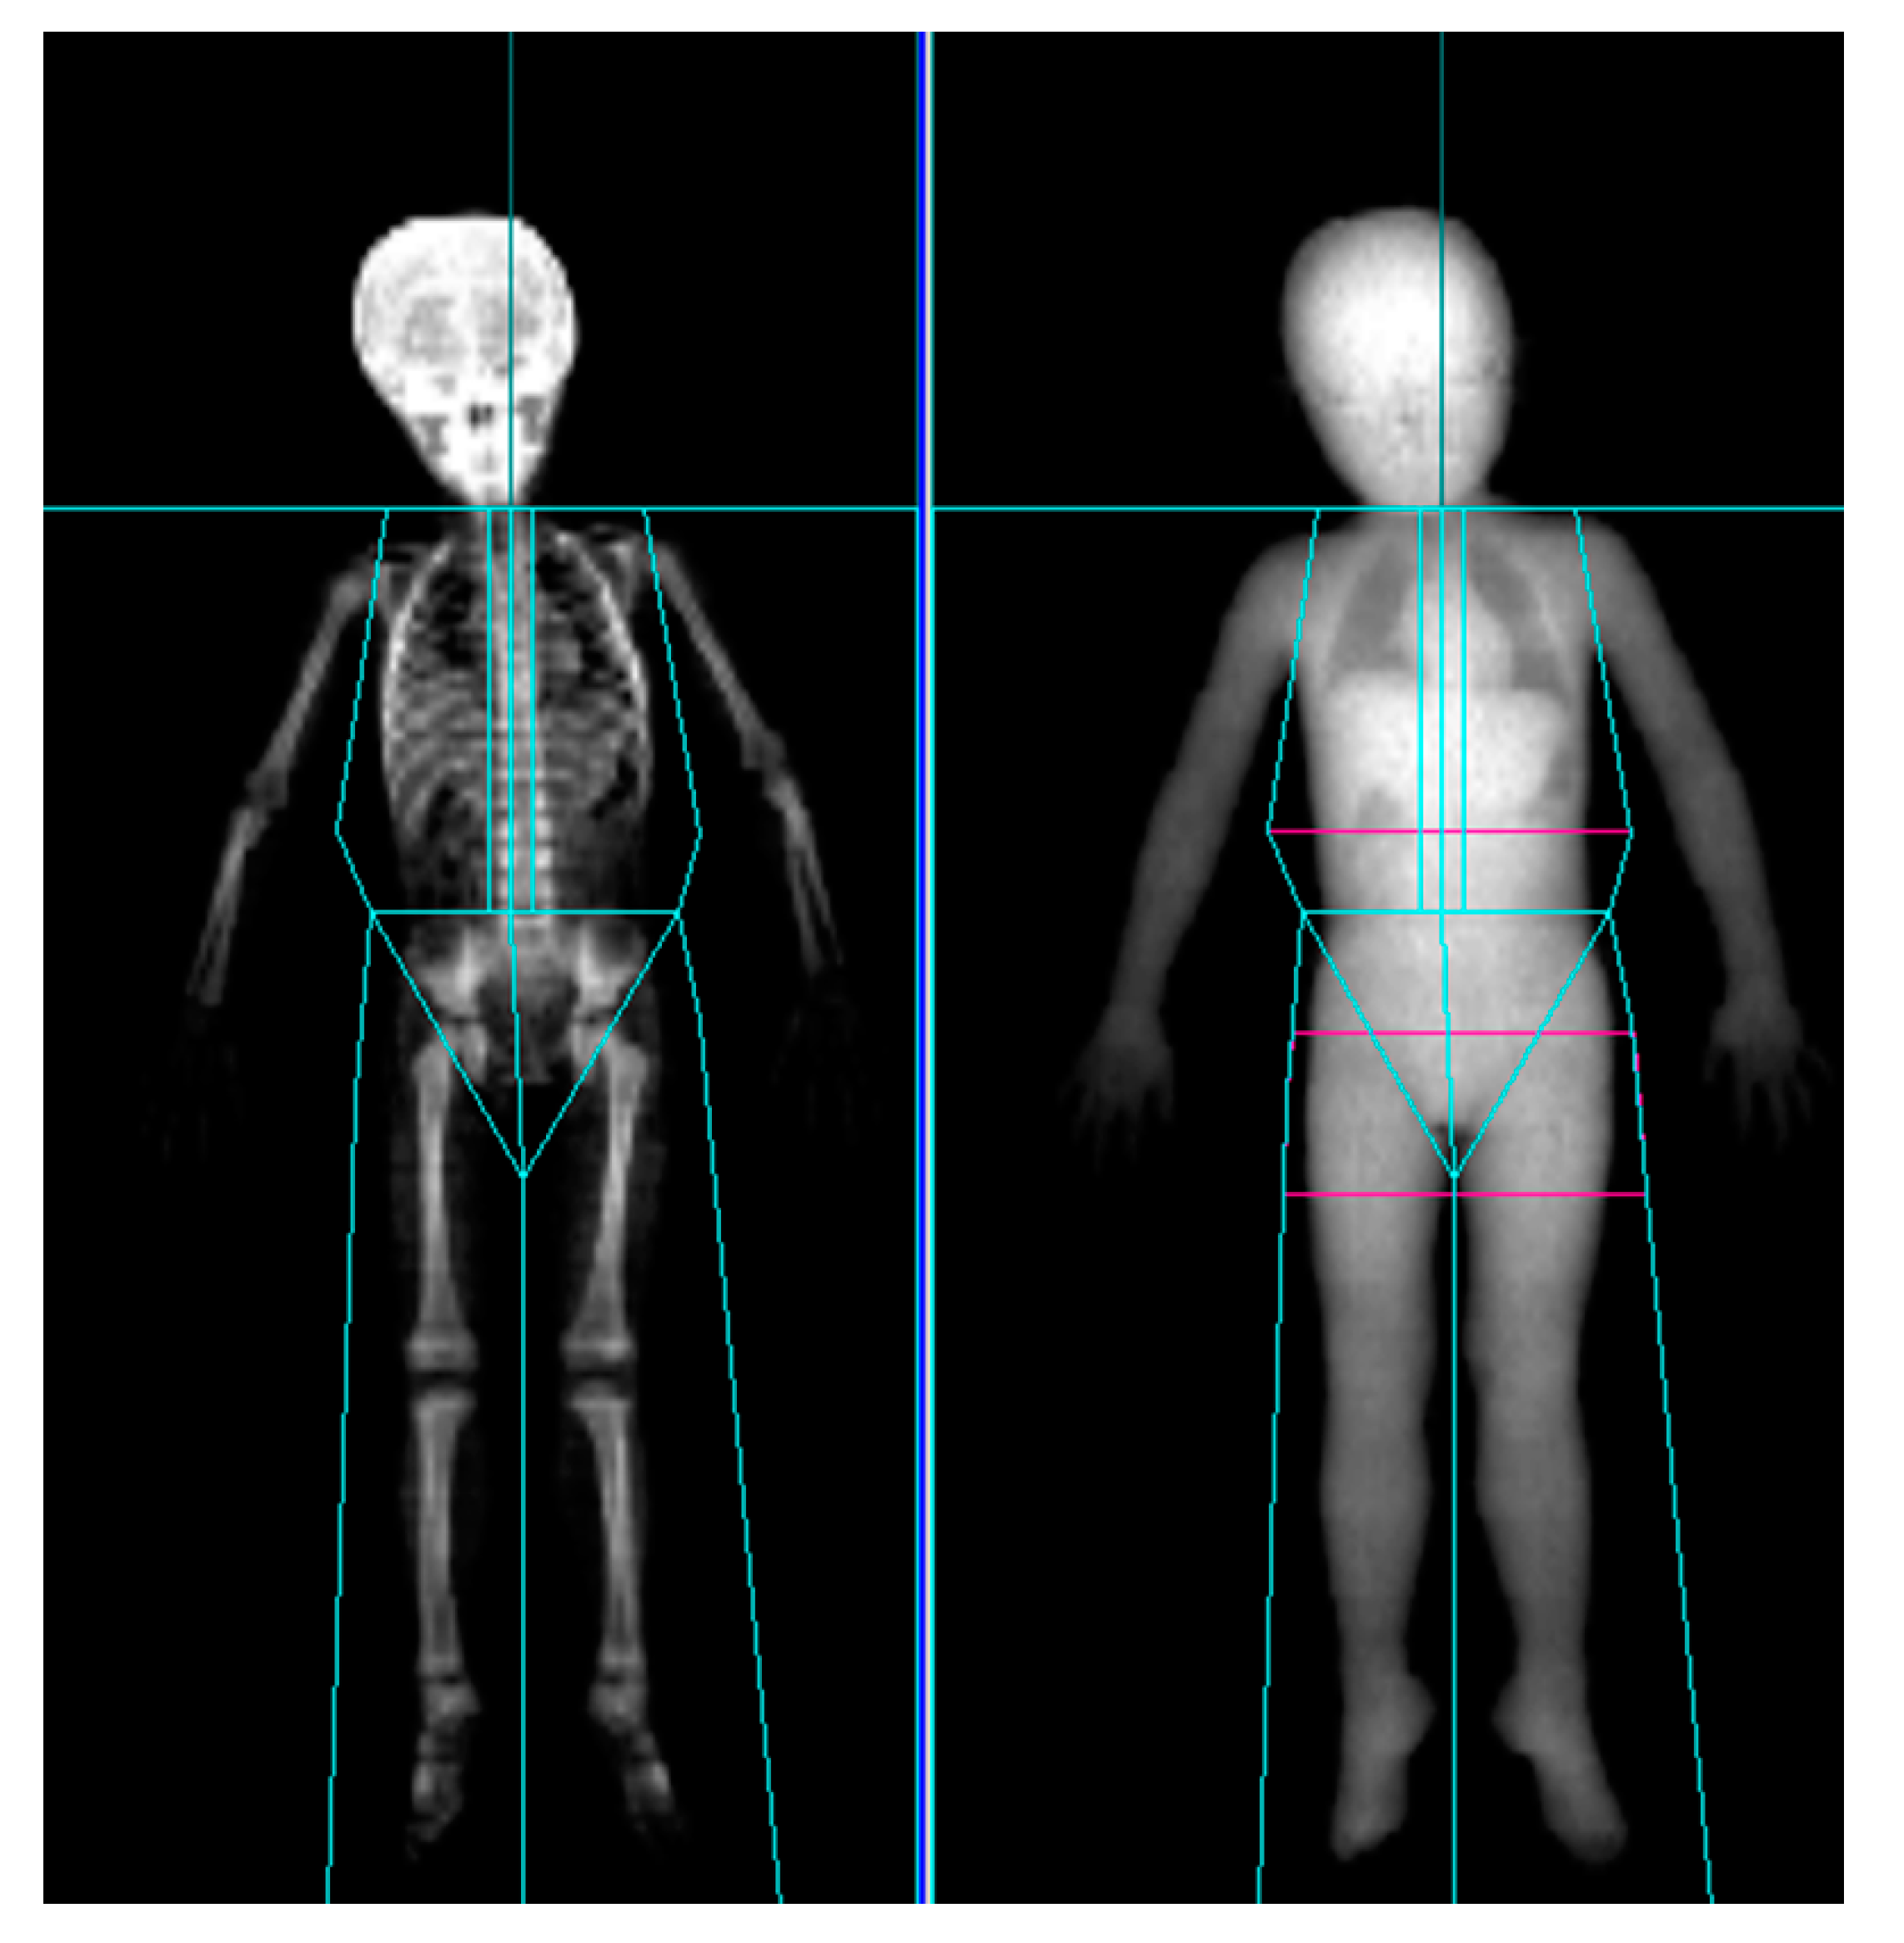

LBM was measured by DXA preinjection as well as at 4 and 12 weeks after injection. At each acquisition, LBM of the affected leg, unaffected leg, and both upper limbs were collected. All participants were scanned using GE Healthcare Prodigy densitometers (GE Healthcare, Madison, WI, USA) in a routine clinical manner, in accordance with the manufacturer’s recommendations. For Prodigy, Encore version 14.1 software (GE Healthcare) was used for the analysis and acquisition (Figure 2). As anatomical landmarks of the arms and legs, lines perpendicular to the axis of the femoral neck and angled with the pelvic brim and center of the arm socket were drawn. Soft tissue extending from the femoral neck to the toes and from the humeral head to the fingertips were included [25,30].

Figure 2.

Dual-energy X-ray absorptiometry scan of a 4-year-old cerebral palsy patient showing positions of regional markers.